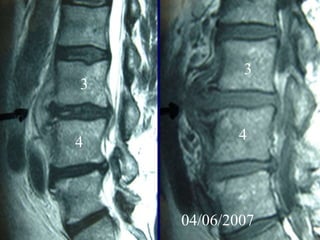

4th case

D.N.

M 61– Cardiologist

Symptoms

 Severe Neurologic deficit

 Intensive Thoracic-lumbar Pain

 High fever

Laboratory

 Neutroph. ↑

 SR 60

PMH

 Heavy smoker

 Diabetes melitus

 Recent Elbow Furuncle (untreated)

Elbow furuncle

3

4 4

04/06/2007

Anterior

PUS evacuation

Bilaterally

Laminectomies

Post posterior PUS

evacuation